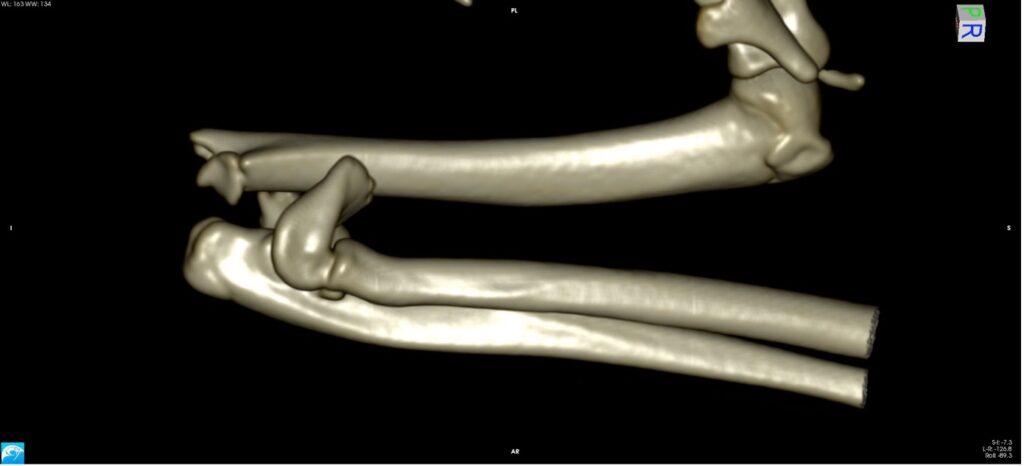

Exemple 3 :

Figure 9 : Pré-Op

Figure 10 : Opération

Figure 11 : Post-Op Immédiat